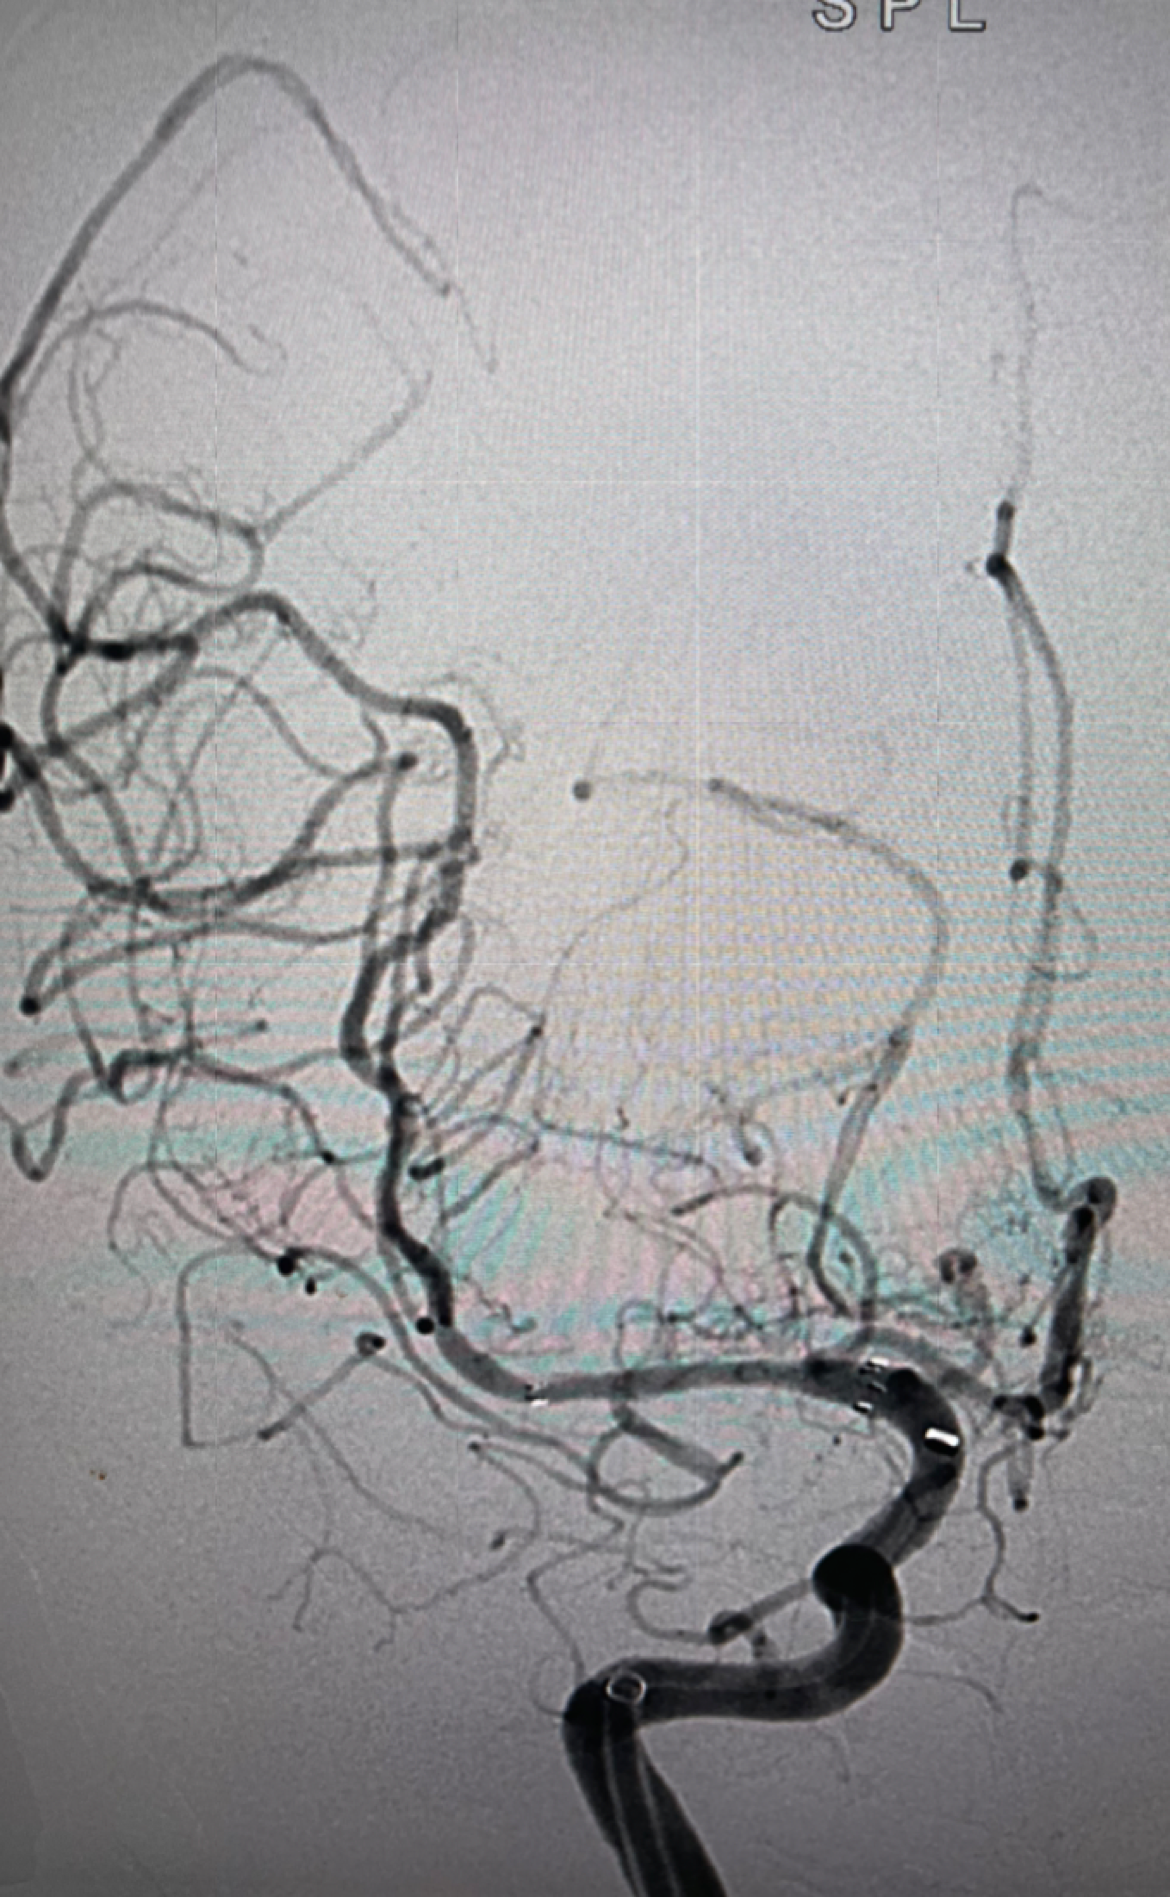

支架打开良好

支架植入后正位造影提示大脑中动脉开通良好